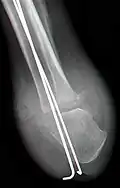

Röntgenaufnahme AP nach tibio-kalkanearer Arthrodese (Pirogoff)

seitl. Aufnahme